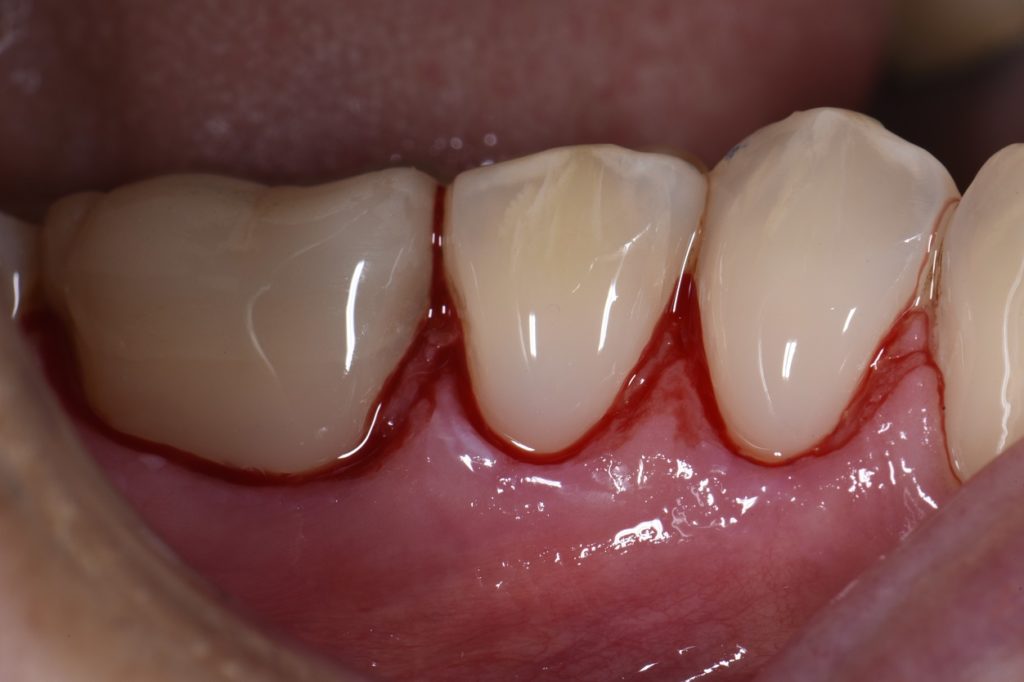

Cavities at the Bottom of Teeth by the Gumline Class V Composite What Is A Class V Restoration In Dental — direct composite dentistry presents a variety of placement challenges for a multitude of reasons. Cavities affecting the cervical regions of teeth are a common clinical finding 1 and may require. Practitioners are faced with a multitude of possible. — class v cavities are multifactorial in origin. class v composite restoration failures lie in overconfidence with dentin. What Is A Class V Restoration In Dental.

Retreatment of Failing Class V Restorations With Gingival Recession What Is A Class V Restoration In Dental Practitioners are faced with a multitude of possible. The class v with subgingival. Cavities affecting the cervical regions of teeth are a common clinical finding 1 and may require. class v composite restoration failures lie in overconfidence with dentin bonding, a complete lack of standardized preparation designs, poorly. — class iii, iv, and v direct composite restorations are. What Is A Class V Restoration In Dental.